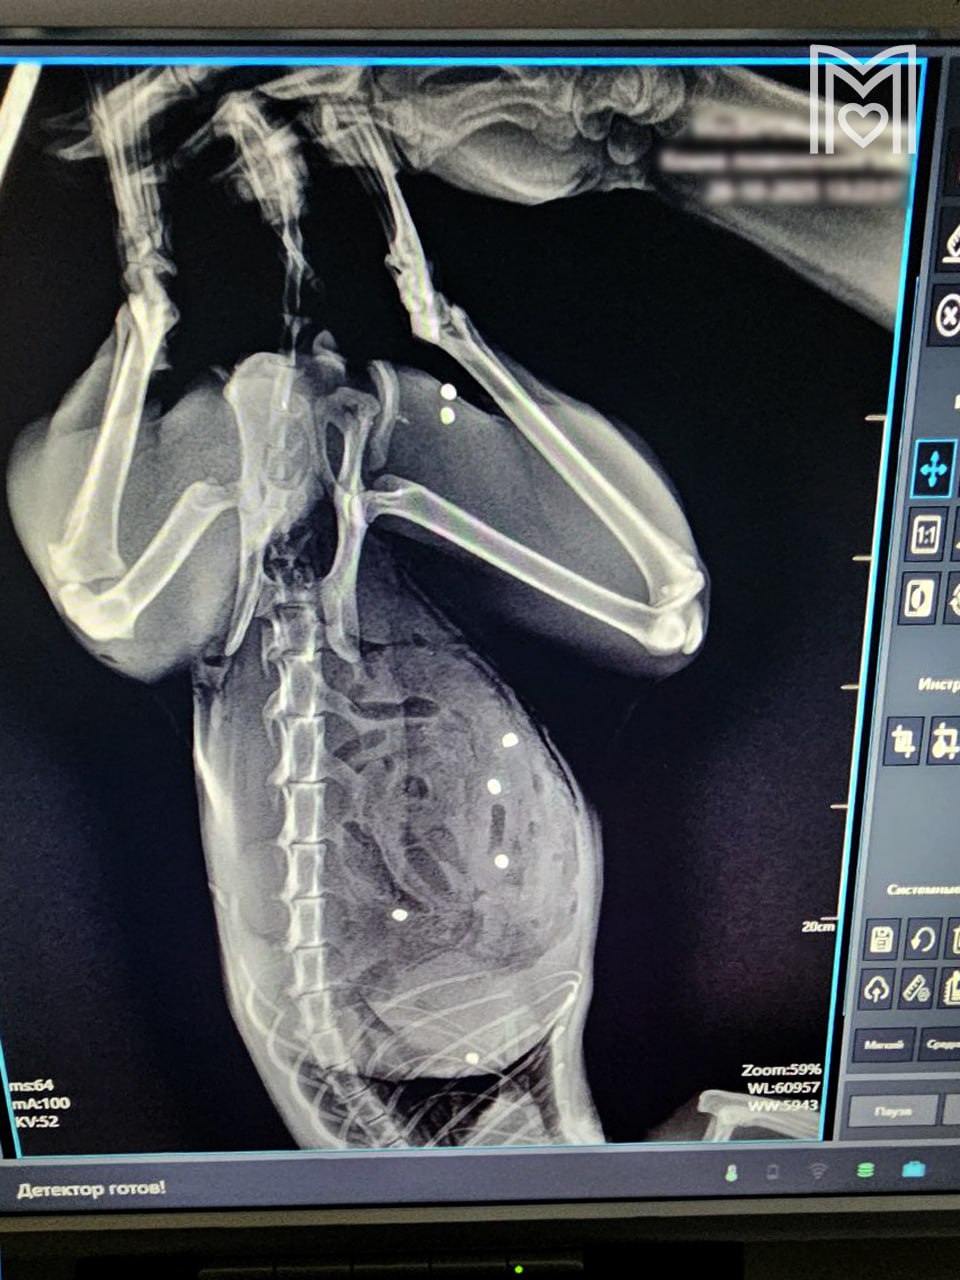

Кота с более чем 20 пулевыми ранениями спасли в ветклинике Зеленограда.

У хвостатого по кличке Тимофей был пробит кишечник в 24 местах и в двух местах селезёнка, также пули попали в грудную клетку и мышцы бедра. По словам владельцев, их питомец пострадал от живодёров во время прогулки в частном секторе.

Хирург немедленно приступил к операции, на которую потребовалось более трёх часов. В итоге почти безнадёжный пациент был спасён, позже его многочисленные раны полностью зажили, сообщает сеть государственных ветклиник Москвы "Мосветобъединение".